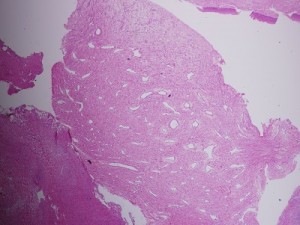

The tumor is composed of spindle-shaped and stellate cells embedded in a collagen matrix and a complex of blood vessels that vary in size from capillaries to large venous channels and have no elastic lamina or elastic fibers; this latter characteristic explains its tendency to easy recurrent bleeding. Thus, severe recurrent epistaxis, occasionally life-threatening, occurs in 63% of patients, second only to unilateral nasal obstruction (91%) as a presenting symptom. Other related symptoms of the disease are nasal discharge, pain, sinusitis, facial deformity, hearing impairment, otitis media, proptosis and diplopia, each reflecting JAN’s mass-effect on its neighbors. These symptoms generally present for 6 months to 1 year before the patient is diagnosed.

The pathology slides are by the kind auspices of Dr. Shanching Ying, Pathologist and Director of Microbiology Lab, Department of Pathology, Mount Sinai Medical Center, Chicago, Illinois.